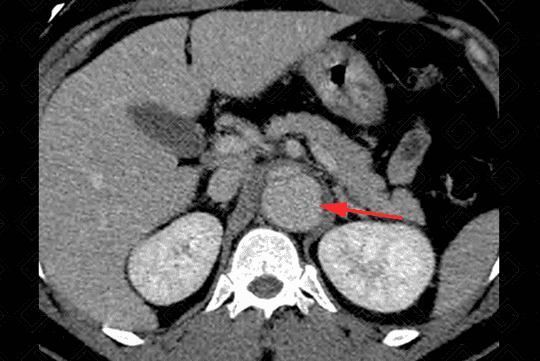

Descrição das imagens: Extensa dissecção da aorta descendente com dilatação da luz falsa (setas vermelhas) e redução das dimensões da luz verdadeira (asteriscos). É importante detalhar o suprimento dos ramos aórticos, ou seja, se estão sendo supridas pela falsa ou verdadeira luz. Neste paciente, observamos que a artéria renal esquerda (seta branca) está sendo suprida pela falsa luz (seta vermelha).

• Figura 4: Pesquisa de complicações: como isquemia, formação de aneurisma, ruptura aórtica e outros.